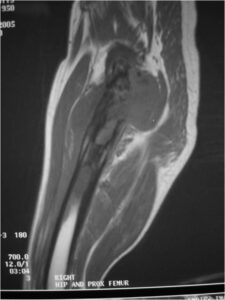

Radiographic Presentation

Radiology emulates pathology: Biphasic Tumor

- One region low grade chondrosarcoma

- Second more aggressive area with bone destruction, lysis of calcification, soft tissue mass

- Cortical permeation and a soft tissue mass in 70% of cases

Ill-defined, lytic intraosseous lesion

- Or extraosseous soft tissue mass

- Devoid of calcifications in continuity with lesions having the features of a cartilaginous tumor

Characteristically abrupt transition between chondroid tumor and dedifferentiated, lytic component

Bone may be expanded and adjacent cortex thickened

Biological Behavior

- Very aggressive locally

- Frequently cortical perforation

- Mass is usually large if extraosseous extension occurs